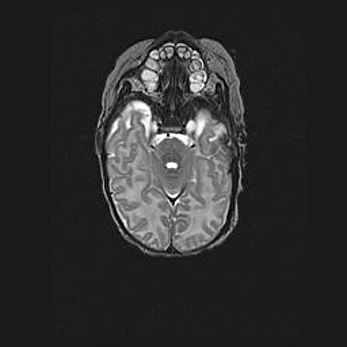

Мальформация Денди-Уокера. Киста задней черепной ямки.

Агенезия мозолистого тела.

Возраст: 2,5 месяца

Вес: 2420 г

Пол: женский

Окружность головы: 37 см

Срок гестации: 32 недели

Мальформация Денди—Уокера — редкий вид патологии ЦНС, представляющий собой врожденный порок развития каудального отдела ствола и червя мозжечка, ведущий к неполному раскрытию срединной (Мажанди) и латеральных (Лушка) апертур IV желудочка мозга. Для этогно синдрома характерна триада симптомов: гипотрофия червя мозжечка и/или полушарий мозжечка, кисты задней черепной ямки, гидроцефалия различной степени. В 70% случаев порок сочетается и с другими аномалиями головного мозга, в частности с агенезией мозолистого тела.